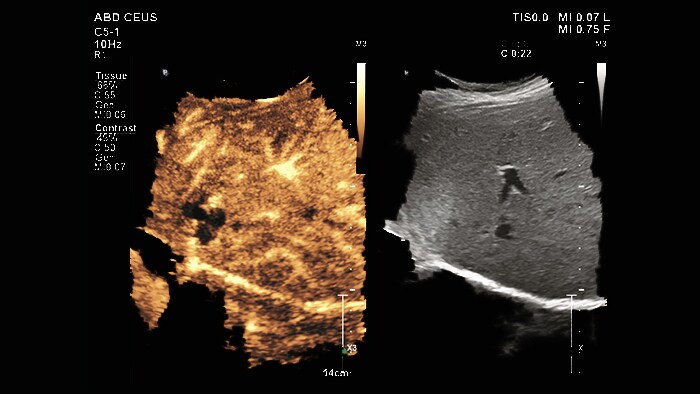

When diagnosing and treating cancer patients, the dynamics of blood flow to and from a suspected lesion can provide clinicians with valuable diagnostic information. For example, blood flow through a liver tumor can offer insights into how likely it is that the cancer could spread. The current standard of care for assessing lesion blood flow requires the intravenous injection of an iodinated contrast media that is not well tolerated by some patients. In these instances, contrast-enhanced ultrasound (CEUS) is rapidly becoming a viable alternative as an increasingly important tool for lesion characterization.

Instead of using an iodinated contrast media, CEUS leverages micro-bubble contrast media, based on an inert gas that is excreted via the patient’s breathing. With the introduction of Philips Microvascular Imaging Super Resolution Contrast-Enhanced Ultrasound (CEUS) on Philips Ultrasound System – EPIQ Elite – CEUS imaging now delivers up to 200% better spatial resolution than previous offerings.

“Philips’ microvascular imaging allows us to visualize the pattern of contrast media flow into a lesion, and also shows how it changes over time, which gives us greater diagnostic confidence in assessing indeterminate lesions,” said Professor Dirk-André Clevert, Professor of Radiology at Ludwig-Maximilians-Universität (LMU), Munich, Germany. “Sharing our knowledge about how to use this latest technology and interpret the results has been greatly enhanced by Philips’ latest Collaboration Live software [1], which allows us to remotely train external sonographers and guide them through procedures.”